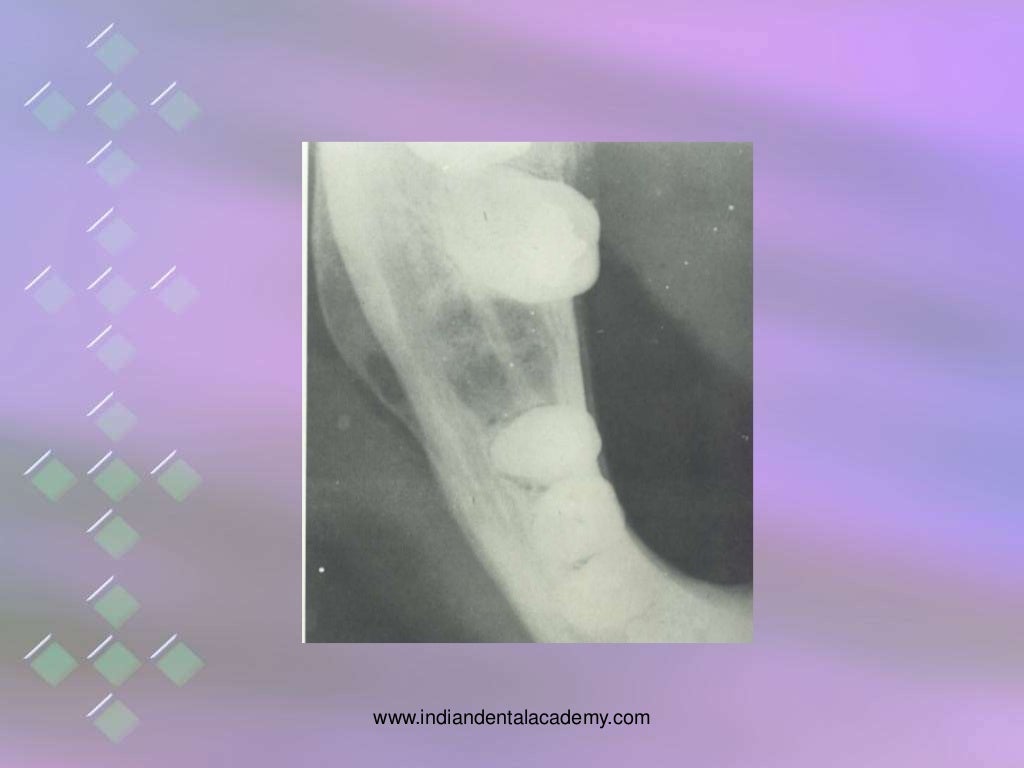

From www.slideshare.net

osteomyelitis of jaw bones / dental implant courses by Indian dental Osteomyelitis Of Implant The knowledge of the real impact of osteomyelitis on the outcome of implant therapy and the identification of risk factors associated with. Much of our understanding of the underlying pathophysiology of osteomyelitis, from the perspective of both host and pathogen, has. Epidermidis) and staphylococcus aureus (s. Reported a case of failed osseointegration after dental implant placement in the area of.. Osteomyelitis Of Implant.